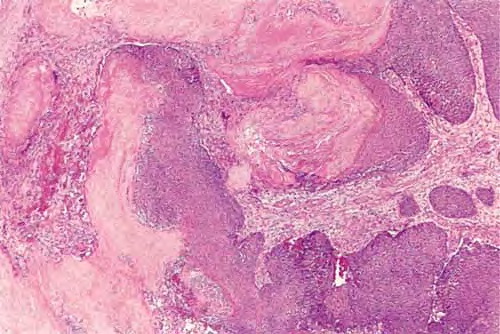

Pilomatricoma shows a spectrum of morphologic features that mainly reflect different evolutionary stages. Early and well-developed pilomatricomas reveal variably sized, round to oval cystic lesions lined by a basaloid epithelium at the periphery and filled in the center with masses of eosinophilic, faulty hair matrix material containing “shadow” (“ghost”) cells

Basaloid (matrical) cells show monomorphous round nuclei with one or more distinctive nucleoli and variable numbers of mitotic figures. Foci of squamoid epithelium are sometimes noted within the epithelial lining. Regressing pilomatricomas display haphazardly arranged foci of basaloid cells and shadow cells as well as an inflammatory infiltrate with multinucleated histiocytic giant cells. Granulation tissue is sometimes noted. Old pilomatricomas reveal no basaloid component but show irregularly shaped, partially confluent masses of shadow cells with foci of calcification or ossification. Melanin deposition, trans-epidermal elimination, and extramedullary hematopoiesis have been described in some pilomatricomas. A peculiar variant with relatively large areas of basaloid cells and small foci of shadow cells (“proliferating pilomatricoma”) is occasionally observed in older adults.